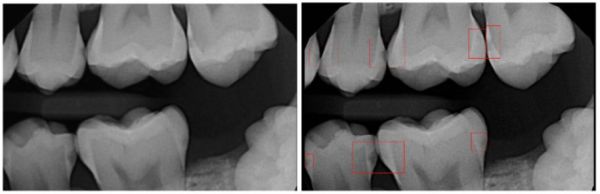

在口腔医疗领域,AI应用最为广泛的也是跟阅片检测相关。拿患病率最高的龋齿来说,传统的诊断依靠X 射线牙片及直接的口内检查,以此发现咬合龋。但对于牙齿根部的龋齿、临间龋和根面龋等潜在龋齿,难以发现,容易漏诊。辅助龋齿检测的AI模型可以代替医生对牙片进行精准的龋齿侦查,这种专项的AI模型对龋齿斑的敏感度高于人类有限的视力。

当然,除了局部专项的阅片外,在整体口腔问题识别上面,AI也有所作为。